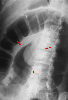

A case of colonic lipoma with intussusception and ulcers in the surrounding mucosa.

X-ray